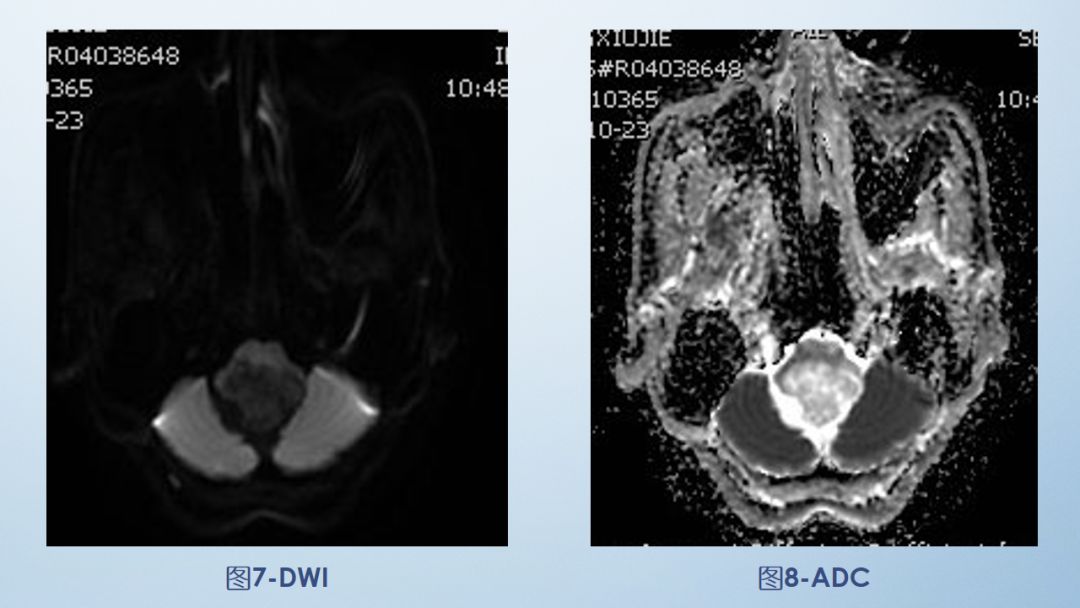

2-FLAIR

FLAIR图及T1矢状位增强:白色箭头所示小脑延髓池内可见实性占位病变,形态不规则,呈分叶状,病变边界清晰,边缘见血管流空信号影如蓝色箭头所示。

影像描述:小脑延髓池内见不规则异常信号影,呈等及稍长T1长T2信号,内部信号不均,边缘见稍粗大流空信号血管影,FLAIR病灶中心少许片状低信号,增强呈明显强化,DWI不均低信号,ADC不均高信号。小脑半球、延髓、第四脑室受压变形。临近延髓受压变窄,呈长T1长T2信号。